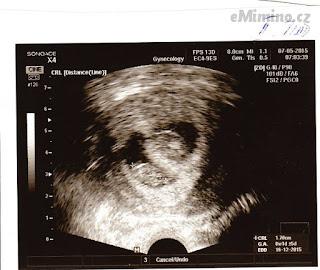

Ultrazvukem je možné rozlišit dva životaschopné zárodky. Vícečetné těhotenství můžeme rozlišit na dvojčata (gemini) a trojčata (trigemini). Samozřejmě můžeme čekat i čtyřčata, paterčata.

7. května 2015 (8+4)

– první miminko 8+1, 1.95cm

– druhé miminko 8+1, 1,73cm